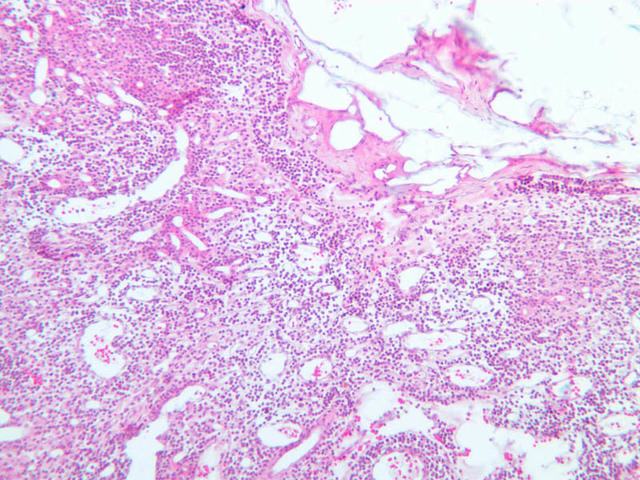

Sections through the spleen (slides A-36, aniline blue [2.5x, 10x, 20x-labeled, 40x] [2.5x, 10x-labeled, 20x-labeled, 40x]; A-37, retic [2.5x, 10x, 20x-labeled, 40x]; A- 37, H&E [2.5x-labeled, 10x, 20x, 40x]; A-38, H&E [10x, 20x, 40x]; A-39, H&E [2.5x, 10x, 20x, 40x]) show a thick investing capsule composed of collagenous tissue and smooth muscle, typically covered with mesothelium. In slide A-36 muscle and collagen are brightly stained. The capsule and mesothelium completely surround the organ and the fibrous portion enters the splenic substance at the hilus around the splenic arteries and veins forming trabeculae of fibromuscular tissue within the splenic substance. This fibromuscular tissue enables the spleen to expel blood by contracting. Identify trabeculae as fibrous partitions in the section and look for blood vessels within them.

Where the trabecular arteries pass into the splenic pulp, they become invested by a sleeve of lymphoid tissue. This lymphatic tissue collectively forms the white pulp of the spleen (A-36 [2.5x, 10x, 20x, 40x]). It also is referred to as the periarterial lymphatic sheath or PALS. On an H&E stained section (A-38 [2.5x, 10x, 20x, 40x] [2.5x, 10x, 20x, 40x]) the white pulp will appear as basophilic clumps of lymphoid cells. The arteries of the white pulp are called central arteries, although they may be displaced to one side of the lymphoid sleeve by the presence of a nodule. The majority of cells forming the PALS are T lymphocytes. In places the covering of lymphatic tissue is enlarged due to the presence of lymphoid nodules (splenic or Malphighian corpuscles) which are comprised predominantly of B lymphocytes.

The remainder of the cellular mass in the spleen is red pulp (A-38 [10x, 20x, 40x]), made up of red and white cells of the blood enmeshed in the reticular tissue of splenic cords and present in the splenic sinuses. After passing through the PALS, the trabecular arteries branch to form smaller arterial vessels known as penicillar arterioles which narrow, forming arterial capillaries that empty into the cords of the red pulp (open circulation) or into the venous sinuses (closed circulation). In the splenic sinuses the cells of the blood are exposed to red pulp macrophages. The splenic sinuses eventually become confluent to form veins that enter the trabeculae and gradually merge meeting in the hilus to form splenic veins.

Examine the composition of the red pulp tissue. The three dimensional structure of the red pulp is analogous to Swiss cheese with the holes being the venous sinuses and the cheese being the parenchyma (i.e. splenic cords). On slide A-36 which is stained with Mallory's aniline blue locate examples of the splenic sinuses ([2.5x, 10x, 20x, 40x-labeled] [10x, 20x, 40x]). The walls of the splenic sinuses consist of adjoining specialized endothelial cells whose nuclei in many cases stand out from the wall in a bead-like fashion. The basement membrane of the epithelial cells stains blue revealing the sinuses quite nicely. Usually the sinus lumen is filled with red cells and leukocytes. The skeletal framework of the cords is provided by a network of reticular fibers. As above, the reticular cells are best seen using a reticular fiber stain (slide A-37 [2.5x, 10x, 20x, 40x-labeled]). Look for the large pale nuclei of reticular cells that have darkly stained reticular fibers. Fibers run irregularly in the cords, but clearly outline the sinuses around which they are wrapped. Notice on this same slide that there is much less reticular tissue in the white pulp than the red. The splenic cords occur around the sinuses and are distinguished by the presence of disintegrating red blood cells undergoing phagocytosis.